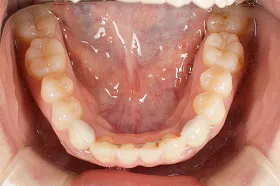

生まれつき歯が生えてこなかったケース

■治療前:生まれつき下顎左右前歯がなく隙間がある

■治療後:矯正治療後、下顎左右3番の2本にインプラント治療

| 主訴 | 生まれつき歯がなく隙間があり、審美障害・咀嚼機能障害がある |

| 治療方法 | インプラント治療 + 矯正治療 |

| 治療期間 | インプラント治療 約6ヶ月 |

| 通院回数等 | インプラント治療 約6回 |

| 費用 | 約94万円(税込) |

| リスク・副作用 | 術後の腫れ・痛み |